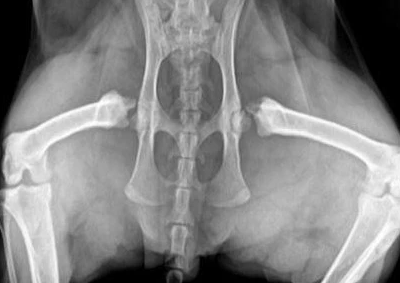

La radiologie thoracique est un élément important de la pratique vétérinaire, mais l'interprétation de la radiologie thoracique est souvent source d'anxiété chez les vétérinaires.Le présent rapport passe en revue les modifications de fond des poumons dues à la maladie, en utilisant une méthode fondée sur la répartition et la modalité.Certaines maladies pulmonaires se produisent de manière caractéristique dans les régions de l 'abdomen crânien ou de la queue des poumons.La combinaison de ces connaissances, associée à la reconnaissance de modes pulmonaires, permet de construire une table logique de tri diagnostique d 'identification.Parfois ambiguë, la radiologie thoracique de l 'ombre du monde va révéler le mystère et la signification de cette méthode d' interprétation pratique.Les cas cliniques seront utilisés pour montrer comment cette méthode permet de faire de la lecture des seins une partie utile de la pratique vétérinaire.